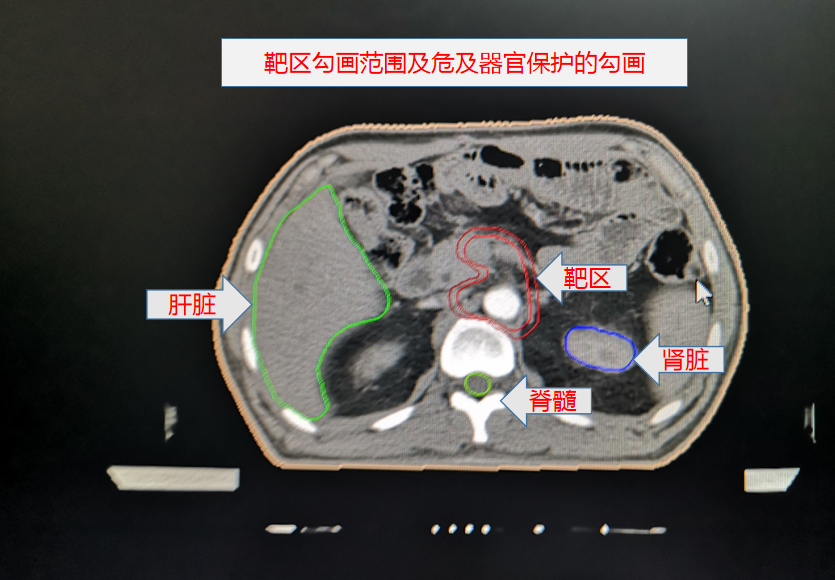

胃癌術後靶區勾畫示例:

其中,胃癌術後規範性預防性放(fàng)療為(wèi)我院首次開展。放(fàng)療前,嚴格按腫瘤放(fàng)療規範和靶區定義勾畫靶區範圍,放(fàng)療期間(jiān),在靶區照射野獲得足夠目标劑量同時(shí),危及器(qì)官受量均在劑量限制标準範圍之内,病人(rén)周圍器(qì)官損傷小,獲益大,實現(xiàn)了(le)真正意義的精準放(fàng)療。放(fàng)療後患者情況穩定,複查各項腫瘤指标均正常,影像學檢查未見異常,得到了(le)上(shàng)級醫(yī)院教授的肯定。